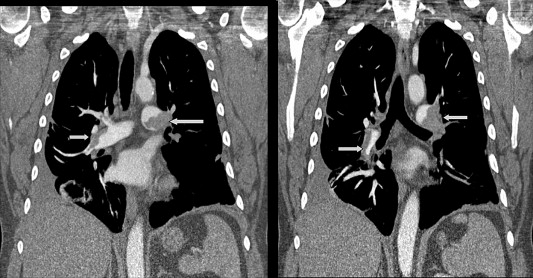

- Focus Area Early Acute Management of the Orthopaedic Injury

- Sponsor PCORI

- Primary Objective RCT to compare Low Molecular Weight Heparin to Aspirin to determine which is the better therapy for preventing death and clinically significant blood clots in the lungs in patients who sustain trauma